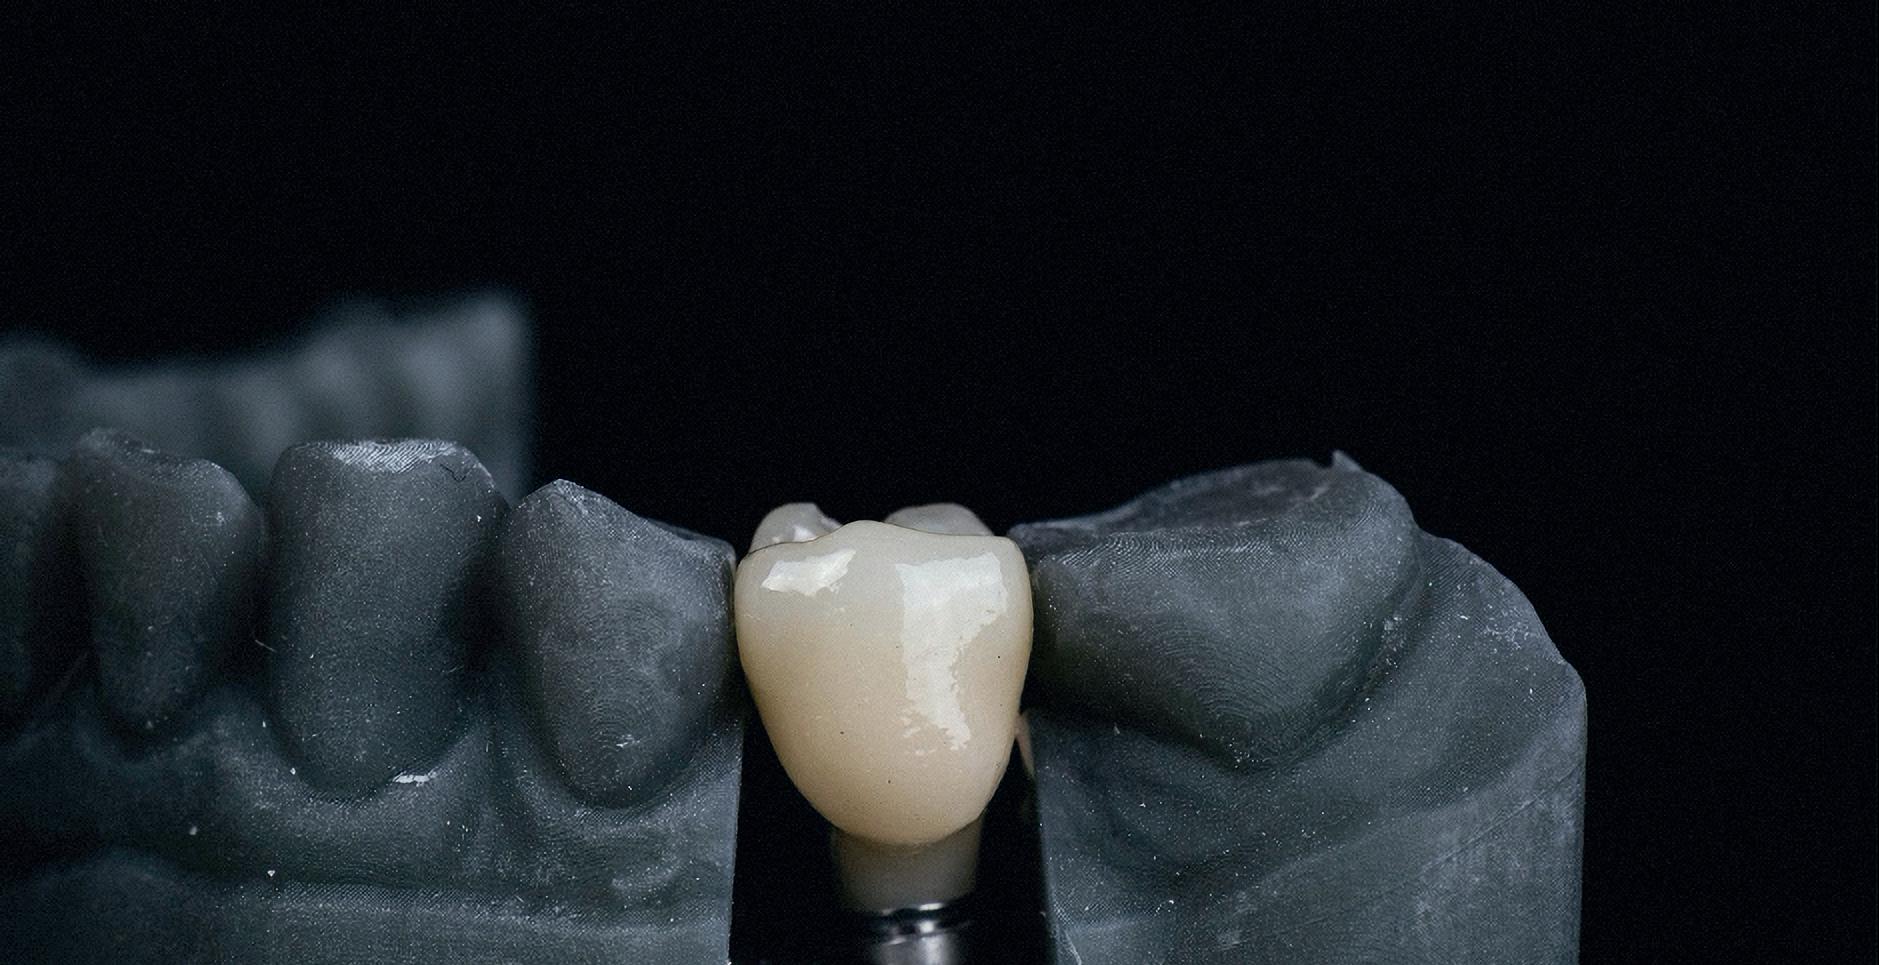

Case 2: Posterior tooth restoration with composite

Restorations with BEAUTIFIL II LS, BEAUTIFIL Flow Plus X and OneGloss by Erik-Jan Muts, M.Sc., Netherlands